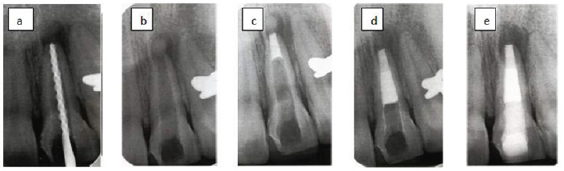

Figure 8: Apeification with MTA as apical plug.

A) The canal is disinfected with copious irrigation.

B) Calcium phosphate is placed through the apex as a barrier.

C) 4mm of MTA is places at the apex.

D) The canal is filled with thermoplastized gutta-percha.

E) Bonded resin resorted is placed at level below CEJ.